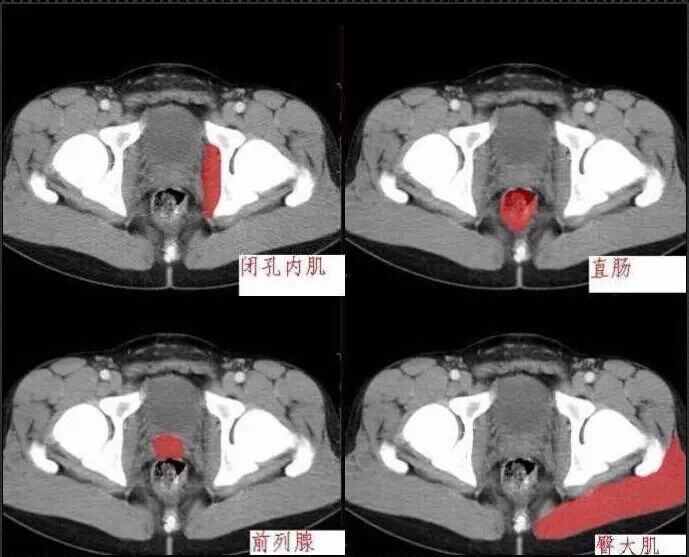

十分钟学会腹部CT解剖(多图)